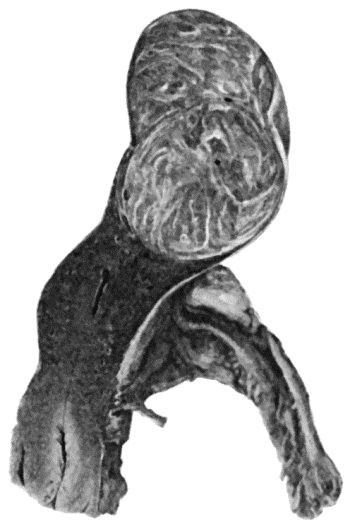

474 135.Cadaver, illustrating the alterations in the Lower Limbs resulting from Ostitis Deformans

475 136.Osteomyelitis Fibrosa affecting Femora